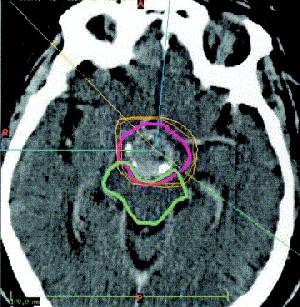

DIAGNOSIS  Preoperatively, the diagnosis of craniopharyngiomas is usually suggested from computed tomographic (CT) or magnetic resonance (MR) imaging. Craniopharyngiomas must be distinguished from other tumors in the parasellar area, including meningiomas, optic gliomas, teratomas, systemic histiocytosis, metastases, and infiltrative disorders such as sarcoidosis.

Calcification in the suprasellar region is seen in about 80 percent of patients with craniopharyngioma and at least one cyst in 75 percent. Thus, a cystic calcified parasellar lesion is very likely to be a craniopharyngioma. MR imaging of the sellar region, including at least one contrast�enhanced sequence, should be sufficient in most instances to establish a preoperative diagnosis. Calcifications can also be seen on plain skull radiographs